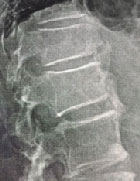

Rachialgie et raideur

Dr Jacques Fechtenbaum Hôpital Cochin - Paris

Mr F., 55 ans, présente des rachialgies diffuses intermittentes d’horaire mécanique, des raideurs rachidiennes et une dysphagie positionnelle. Voici ses radiographies :